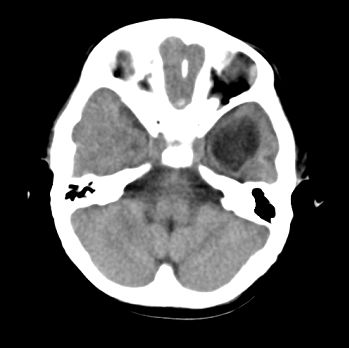

以下是引用22222222在2008-6-9 21:03:00的发言:[br]病灶周围见脑组织包绕,上部可见等或稍高密度壁环绕,壁且见小点钙化-----考虑皮样囊肿或表皮样囊肿可能,但侧脑室颞角内病灶不排除.